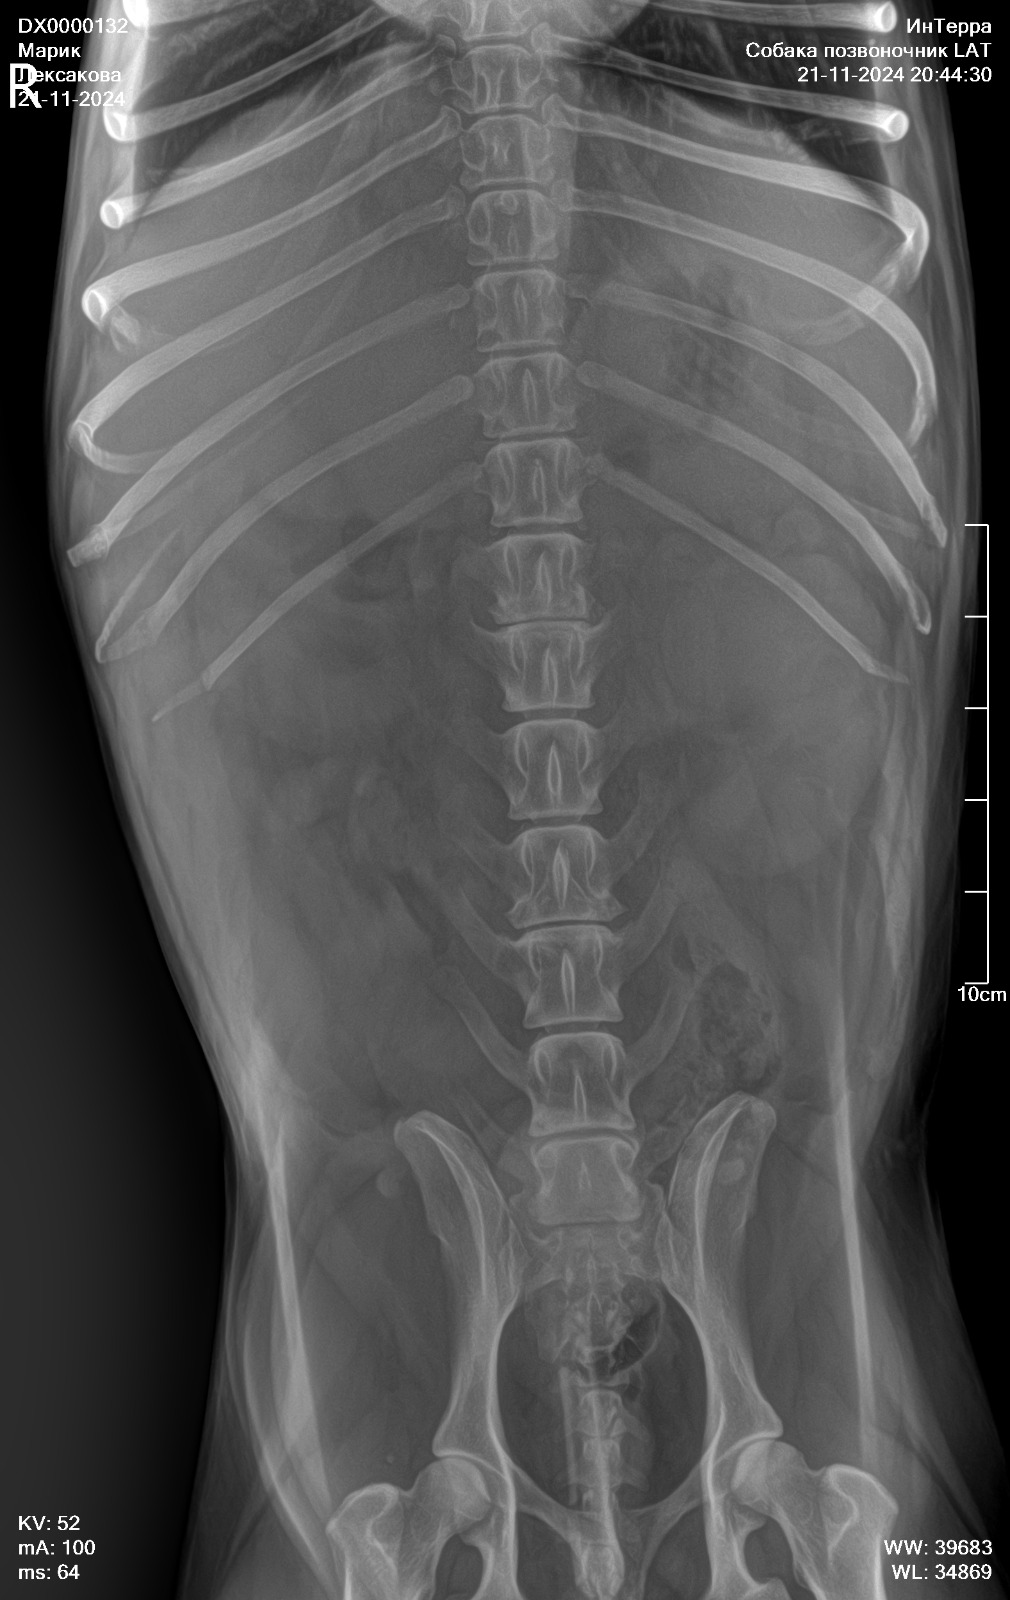

Рентген позвоночника

Вложения

IMG-20241121-WA0054.jpg

IMG-20241121-WA0047.jpg

IMG-20241121-WA0045.jpg

IMG-20241121-WA0034.jpg

IMG-20241121-WA0041.jpg